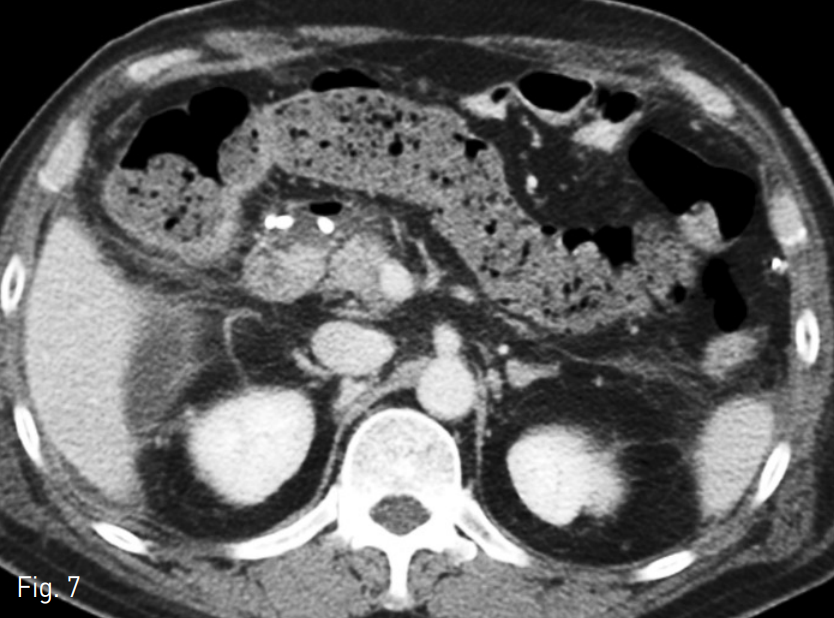

수술 후 10일 째에 시행한 전산화단층촬영에서 식도 소장문합부위 하방과 췌장후방구역, 십이지장 절단 끝의 앞쪽으로 구획화된 액체 저류가 있고 오른 결장주위 공간으로도 액체저류가 있음. 해당 액체 저류들은 미약한 조영 증강이 동반되어 있어 감염된 액체 저류의 가능성이 있고, 이와 같은 소견은 식도소장문합부위 또는 십이지장 절단 끝의 누출 가능성을 시사하는 소견임 (Fig. 1).

Fig. 1

A-B. Contrast-enhanced axial CT scan shows localized fluid collection in extent of inferior aspect of esophagojejunostomy site, retropancreatic area, anterior aspect of duodenal stump, and right paracolic gutter.